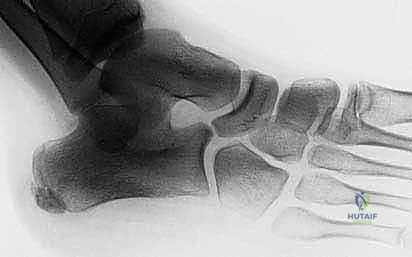

2. التصوير بالأشعة السينية (X-rays)

تعتبر الأشعة السينية الخطوة الأولى في التصوير الإشعاعي. يتم أخذ صور بوضعيات مختلفة (أمامية خلفية، جانبية، ومائلة).

* علامة أنف آكل النمل (Anteater Nose Sign): في الصورة المائلة، يظهر العظم العقب مستطيلاً وممتداً نحو العظم الزورقي بشكل يشبه أنف حيوان آكل النمل. هذه العلامة الإشعاعية كلاسيكية ومؤكدة للالتصاق بين العقب والزورقي.